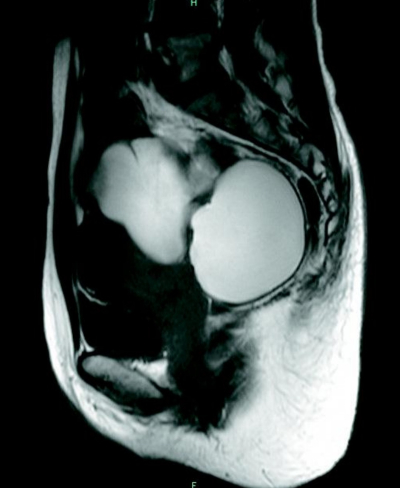

身長 162 cm、体重 58 kg。体温 36.8 ℃。脈拍 68/分、整。血圧 108/76 mmHg。心音と呼吸音とに異常を認めない。下腹部に圧痛のある腫瘤を触知する。内診では、子宮は前屈で正常大。左右付属器の腫瘤はそれぞれ径 10 cm で圧痛を認める。Douglas 窩に有痛性の硬結を触知する。下腹部 MRI の矢状断像を別に示す。

T2強調像